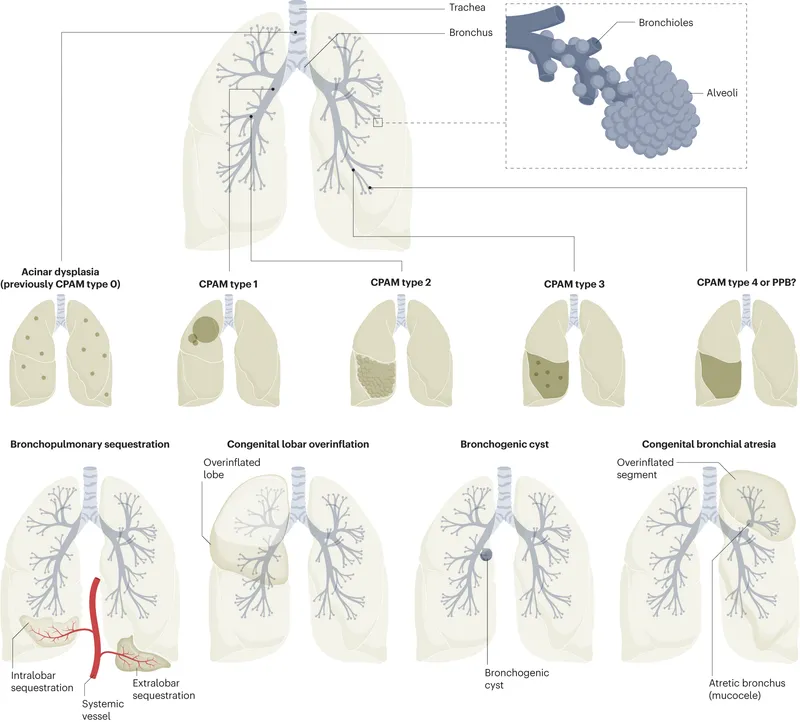

- Congenital Lung Malformations (CLMs): Spectrum of structural defects in lung parenchyma, airways, or vasculature due to abnormal development.

- Hamartomatous lesion; abnormal branching of immature bronchioles & alveoli.

- Stocker Classification (Types 0-4):

- Type 1: Most common (~65%), large cysts >2 cm.

- Type 2: Small cysts <2 cm; associated anomalies.

- Type 3: Microcystic/solid; poor prognosis if large.

BPS (Bronchopulmonary Sequestration) - Rogue Lung Raiders

- Non-functional lung tissue; lacks normal communication with the tracheobronchial tree.

- Key feature: Anomalous systemic arterial supply, typically from thoracic or abdominal aorta.

- Two main types:

- Intralobar (ILBPS): More common (~75-85%). Located within normal lung lobe/pleura. Venous drainage usually to pulmonary veins. Presents later (childhood/adulthood) with recurrent infections.

- Extralobar (ELBPS): Less common (~15-25%). Has its own pleural covering. Venous drainage to systemic veins (e.g., azygos, hemiazygos, IVC). Often diagnosed in neonates (respiratory distress); associated with other congenital anomalies.

- Congenital Lobar Emphysema (CLE):

- Progressive lobar overinflation; air trapping.

- Cause: Bronchial cartilage defect (most common).

- Bronchogenic Cysts:

- Foregut anomaly; abnormal tracheobronchial budding.

- Location: Mediastinum, intrapulmonary.